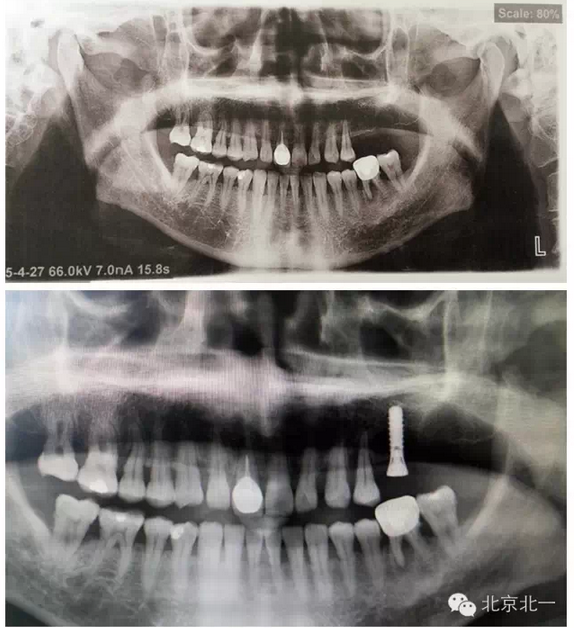

7 植體備份不合理, 無(wú)備骨粉骨膜, 術(shù)中情況特殊,需要植骨蓋膜。(圖七、手術(shù)沒(méi)有PLAN

B計(jì)劃,無(wú)骨粉骨膜,無(wú)大一號(hào)種植體,,有CBCT,拔牙后已經(jīng)2年,打開(kāi)后拔牙窩沒(méi)有愈合,要植骨有木有,只能放棄一顆植入,等待下一次了)